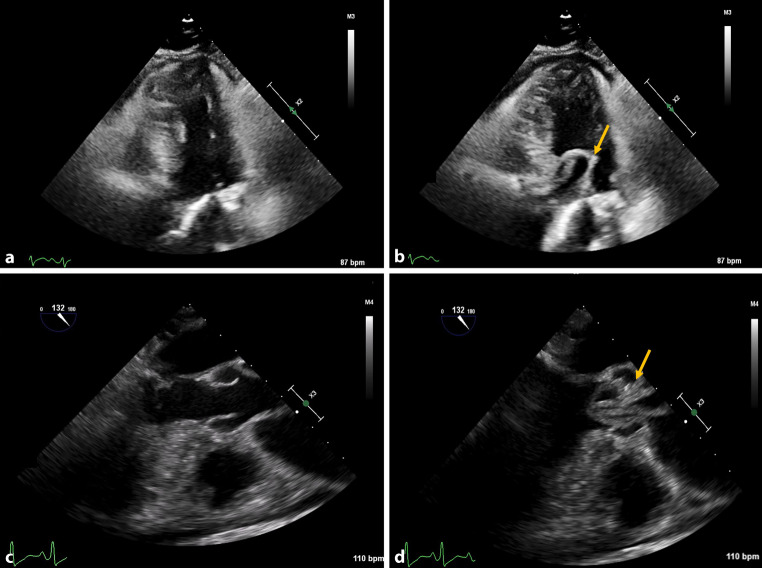

Intimointimal intussusception in acute aortic dissection: a rare phenomenon.